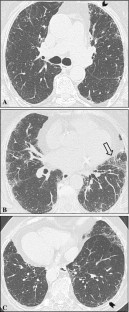

Fig. 4